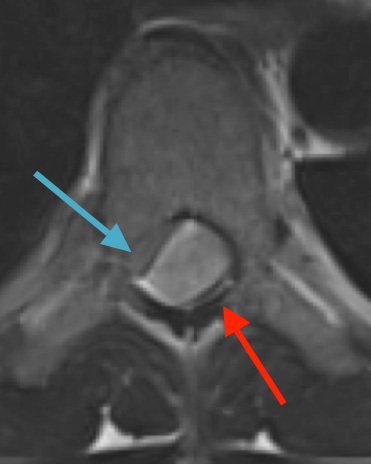

Preoperative MRI T1w demonstrating a large enhancing tumor (red arrow) causing severe cord compression and displacement (blue arrow)

Preoperative MRI T2 demonstrating obstruction of CSF around the cord (blue arrow), resulting from the tumor (red arrow)